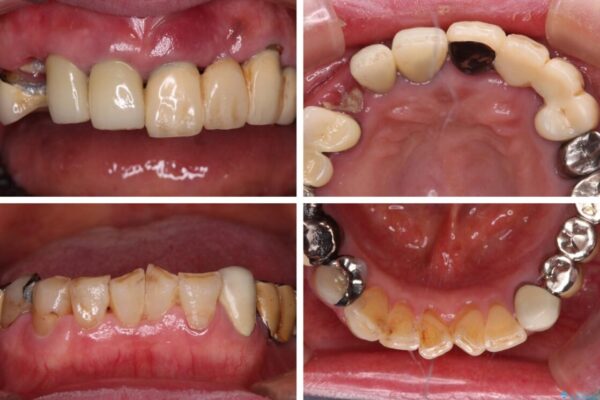

抜歯の必要な前歯や、以前治療した前歯のクラウンの外観を気にして来院された患者様です。

クラウンが不適合であったり、根管治療の必要なほどの痛みのある歯であったり、見た目の気になる前歯などをオールセラミッククラウンに補綴治療を行うこととしました。

治療前

• 前歯をきれいにしたい インプラントや部分矯正を用いた総合歯科治療 治療前画像